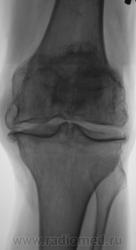

Боли в коленном суставе.

Деформирующий гонартроз 4 ст. или есть какой-то подвох? Двойной контур суставной поверхности медиального мыщелка бедра не Кениг ли случайно?

я бы по коссинской 2-3 ст. деформирующего артроза написала, ито 3 ст это когда уже совсем не прослеживается суставной щели, а здесь она есть.

Согласен с DR.RAD двухсоронний гонартроз 2-3степени.

Мне показалось, что суставная щель вовсе и не так уж сужена.А вот в пателло-феморальный суставе резкое сужение суставной щели.Выраженный субхондральный склероз, краевые остеофиты суставных поверхностей костей.А что там у Косинской по этому поводу написано, помните?